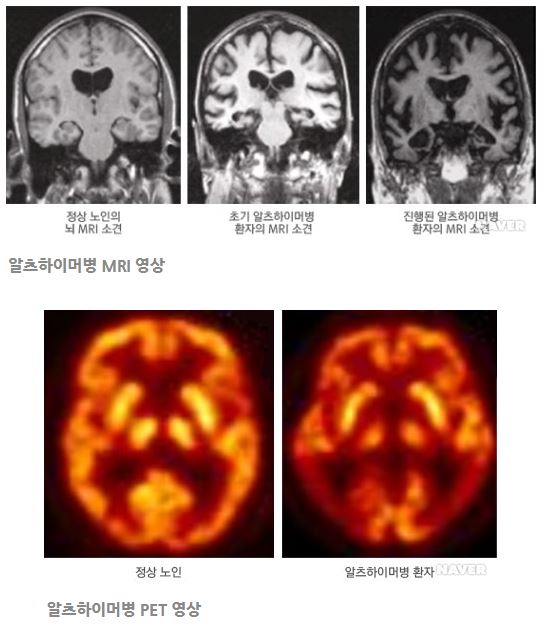

고가의 장비 필요: 양전자 방출 단층 촬영(PET)이나 MRI(자기공명영상)와 같은 고가의 장비를 사용해야 하므로, 이러한 검사를 반복적으로 수행하기 어렵습니다. 이는 특히 의료 접근성이 떨어지는 지역에서 큰 문제로 작용합니다.

신경 세포 손상: 알츠하이머병에서는 뇌의 특정 부위, 특히 기억과 관련된 해마와 대뇌 피질에서 신경 세포가 손상됩니다. 이로 인해 뇌의 구조와 기능이 변화하게 됩니다.